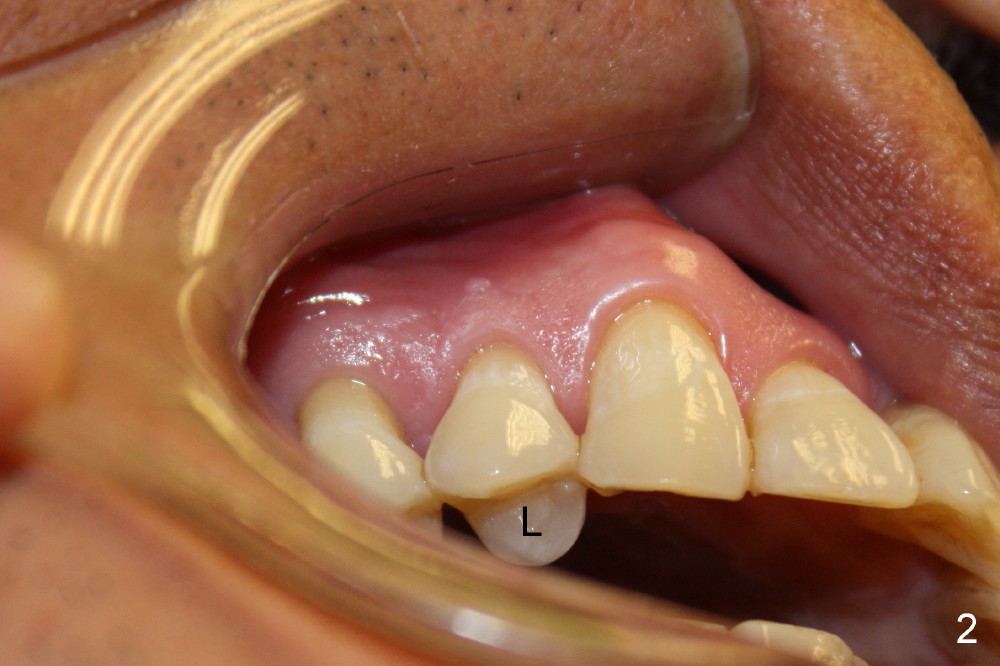

A 56-year-old man fractures the lingual cusp of the upper right 1st premolar (Fig.1,2).

A provisional is fabricated immediately after extraction and implant and definitive abutment placement (Fig.3,4: P). The provisional hold the papilla in place (Fig.3 *). There is no occlusal contact with the opposing dentition (Fig.4 ^). The gingiva looks purplish due to difficult extraction. The tooth keeps fracturing while being extraction. The bone is dense. On the other hand, the dense bone helps achieve primary stability of the implant.